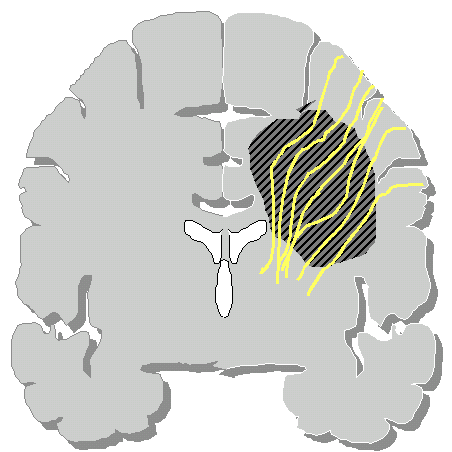

Un glioma può essere quindi distinto in tre tipi (Daumas-Duport): |

Tipo

I: lesione circoscritta |

II: lesione compatta ed area di tessuto cerebrale infiltrato |

III: lesione diffusa con parenchima infiltrato |

|

Grazie alla tecnologia attuale, una massa tumorale compatta, che sposta il tessuto cerebrale può essere asportata praticamente da qualsiasi sede. La parte infiltrante invece potrà essere asportata solamente se questa interessa aree non critiche altrimenti il rischio di danni è molto alto. Parlando però di gliomi, la componente infiltrante è quasi sempre presente.